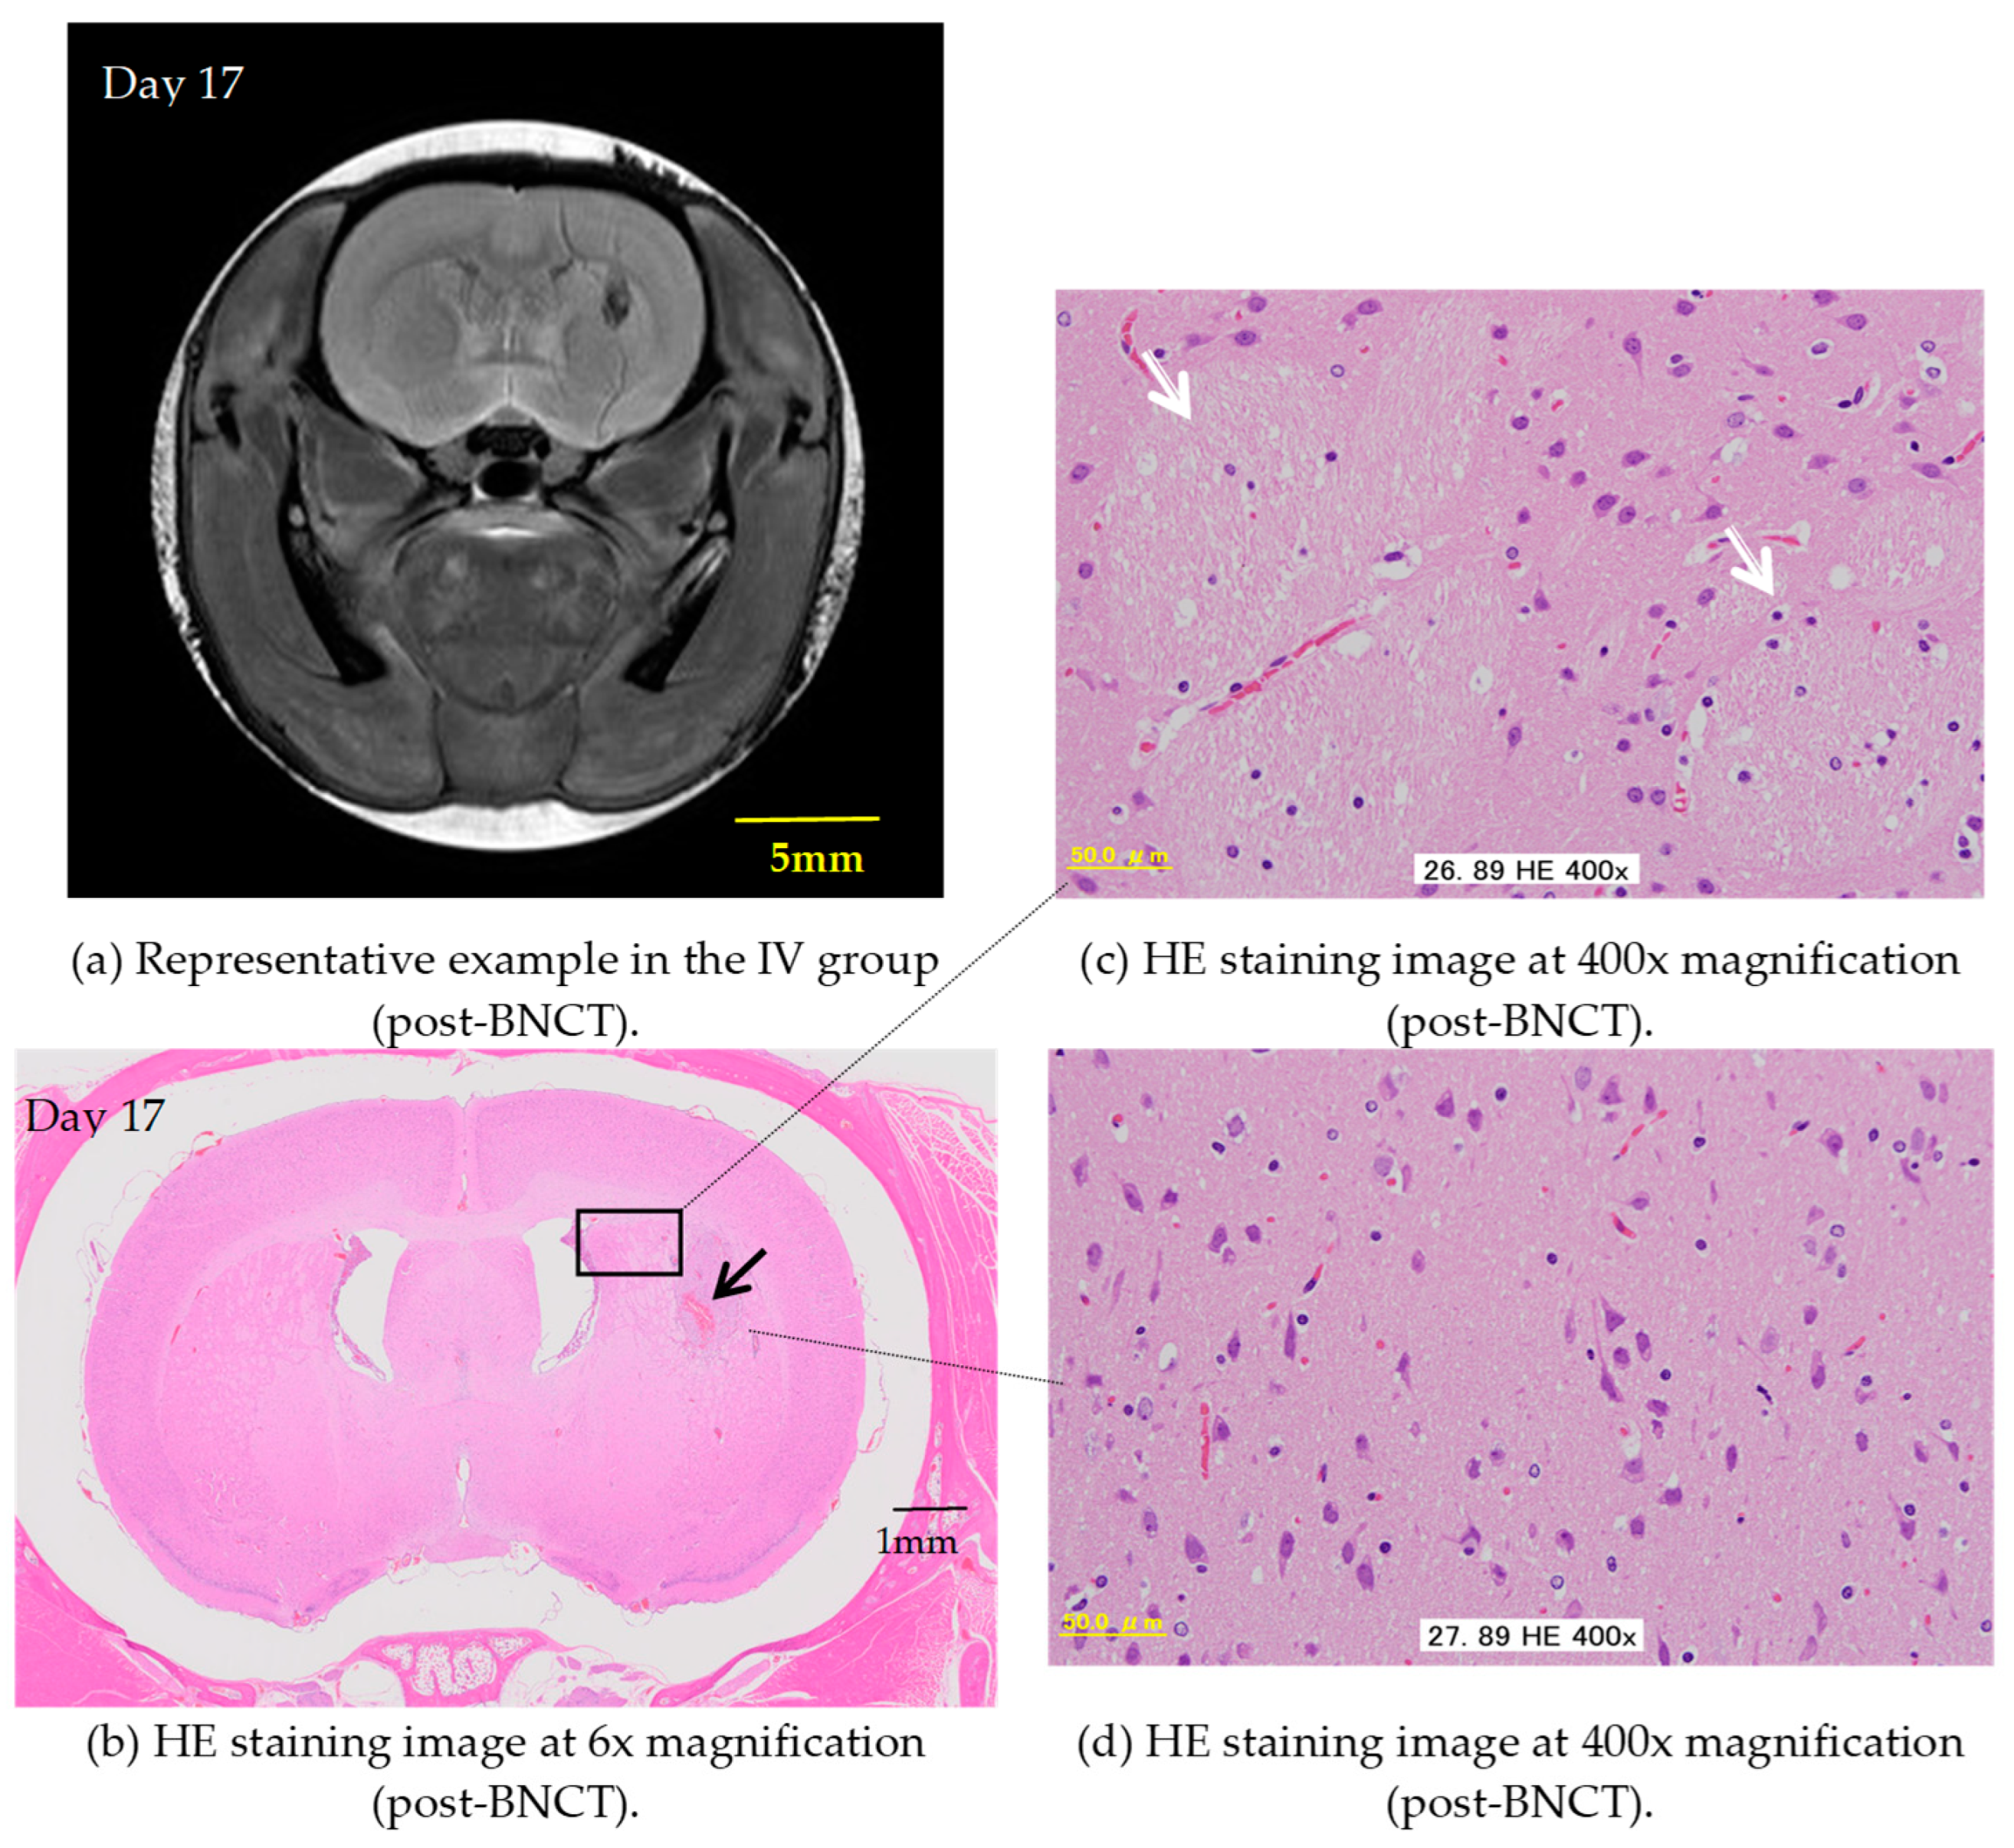

2.2. BNCT Effect on the CSF Administration Method of 10BPA

2.3. Pre- and Post-Treatment MRI Assessment

2.4. Hematoxylin and Eosin Staining of C6 Rat Glioma Brain Sections

3. Results